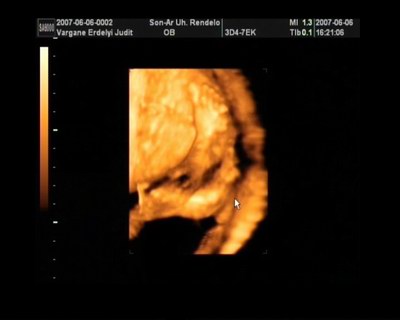

Melcsi! Nagyon határozott arcocskája van a fiadnak, karakteres, gyönyörű kispasas!